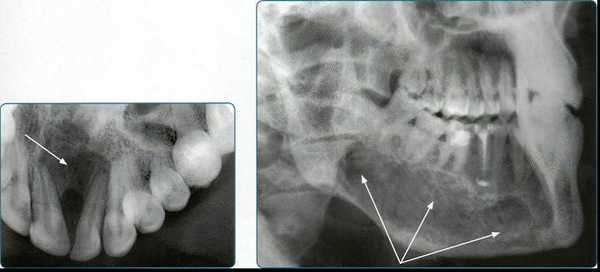

Признаком наличия кистозной полости является образование округлой или овальной формы достаточно однородной структуры с четкими ровными контурами. При лучевой диагностике радикулярной кисты удается проследить связь кистозной полости с верхушкой

корня зуба. Нередко корень зуба проникает в полость кисты. В структуре фолликулярной кисты всегда определяется коронковая часть непрорезавшегося, как правило, полностью сформированного зуба. На рентгенограммах изучаются такие симптомы: форма и размер кистозной полости, локализация, состояние кортикальных пластин челюсти, однородность структуры, наличие внутриполостных перегородок, степень деструкции костей и состояние зубов в проекции кисты. Контактные внутриротовые рентгенограммы обладают достаточной информативностью для определения кист небольших размеров и оценки состояния пародонта. При кистах больших размеров они не дают полной информации о рентгенологических признаках, а что особенно важно, не позволяют в полной мере оценить окружающие области, например верхнечелюстной синус. На рентгенограмме происходит суммация теней различных образований челюстно-лицевой области, что создает трудности при изучении рентгенограмм Радиовизиография с последующим компьютерным анализом оптической плотности изображения является диагностически значимым методом для оценки плотности костной ткани. Ее проводят для контроля процесса остеорегенерации в области костного дефекта после оперативного вмешательства.

Компьютерный томограф позволяет на основании стандартных изображений в аксиальной плоскости моделировать изображения лицевого отдела головы в любых произвольных проекциях для улучшения пространственной визуализации. Современные компьютерные томографы, имеют высокую разрешающую способность за счет возможности создания тонких срезов тканей. С применением оптической денситометрии удается определить структуру костной ткани в очаге деструкции, структуру содержимого кистозной полости, объективно оценить динамику восстановления костной ткани в патологическом очаге в процессе лечения. На компьютерном томографе с использованием трехмерной реконструкции можно установить «причинный» зуб, определить форму, истинные размеры кисты, направление ее роста и характер взаимоотношения с окружающими тканями. С помощью КТ может быть проведена дифференциальная диагностика между одонтогенной интрасинусальной кистой и истинной кистой пазухи путем выявления костной перегородки, отделяющей полость истинной кисты от полости пазухи, отсутствию связи с корнями зубов. МСКТ высокоэффективна в диагностике кист, но несет значительную лучевую нагрузку. МСКТ также требует оптимизации алгоритмов обследования и интерпретации полученных изображений в контексте стоматологической и челюстно-лицевой специфики с акцентом на определенные анатомические структуры. Перспективным направлением лучевой диагностики являются конусно-лучевые компьютерные томографы. Трехмерная конусно-лучевая компьютерная томография значительно увеличила возможности дифференциальной диагностики в специализированной амбулаторной стоматологии и челюстно-лицевой хирургии. В основе конусно-лучевых томографов используется рентгеновский луч конусной формы. Рентгеновский луч проходит через ограниченный объем ткани, с размером ребра куба не более 15 сантиметров, в итоге получается первичное трехмерное изображение высокого разрешения при минимальной дозе облучения. Конусно-лучевой томограф дает цифровое изображение высокого разрешения изучаемого объекта в трех плоскостях. С помощью конической формы луча толщина среза может быть установлена от 0,125 мм до 2 мм. При этом лучевая нагрузка на пациента в 6-10 раз меньше, чем при проведении стандартной спиральной компьютерной томографии.